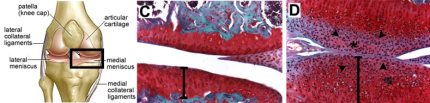

Osteoarthritis occurs when the articular cartilage that lines the surfaces of the joints becomes damaged. This can happen due to acute trauma, or as a result of aging.

Articular cartilage is a thin layer of w

hite, glossy tissue that covers the ends of the long bones where they meet to form the joints of the arms and legs. The function of articular cartilage is to facilitate mobility by providing a smooth surface for the ends of the bones to glide against one another; and support for shock-absorption during load-bearing.

Cartilage tissue is comprised of cells called chondrocytes, and the material that surrounds the cells which is called matrix. Cartilage matrix contains fibers, proteins, glycosaminoglycans and water. It provides structural integrity and resilience to the tissue. The matrix is synthesized (and broken down) by the chondrocytes within it.

We found that in mice, genetic activation of EGFR signaling stimulated proliferation and matrix synthesis by articular cartilage stem cells, nearly doubling the thickness of the articular cartilage.